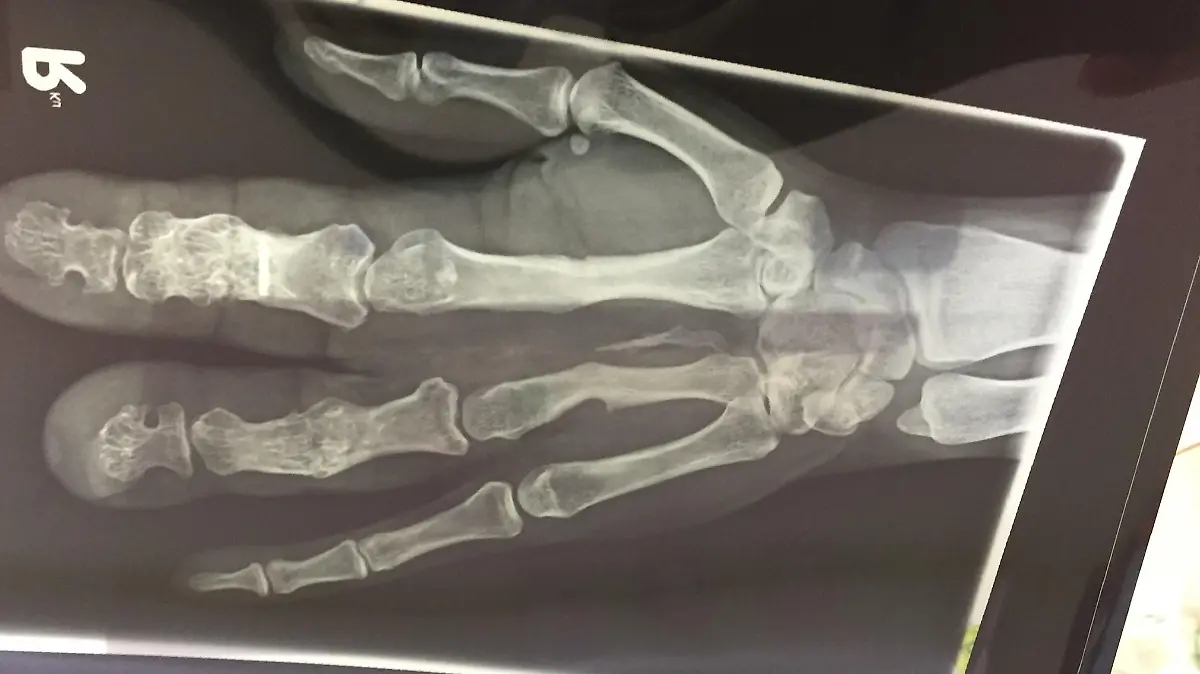

„Man ist machtlos, wenn die Ärzte sogar machtlos sind. Ich kämpfe, mache einfach weiter, versuche alles hinzubekommen.“ Der Kampf gegen die Krankheit dauert schon ihr ganzes Leben. Yasemin hat das Proteus-Syndrom. - ein genetischer Defekt, der als Kind ihre Finger überdimensional groß wachsen ließ. Schon im Alter von drei Jahren mussten ihr die ersten Gliedmaßen amputiert werden.

Als Teenager schämt sie sich für ihre entstellten Hände, versucht sie zu verstecken. Sie ist anderen Menschen gegenüber zurückhaltend, doch mit den Jahren wird Yasemin selbstbewusster – ihre Krankheit greift allerdings immer mehr um sich. Zwei weitere Finger mussten entfernt werden.